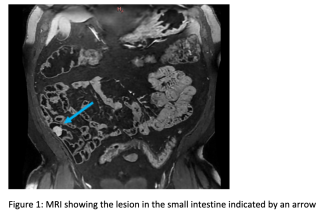

A 60 year old man presented with spoliative anemia. He is not known for cutanous macules around the mouth. An initial work up by colonoscopy and gastroscopy revealed a Helicobacter pylori infection without other significant abnormalities. Subsequently, a magnetic resonance imagery was performed and a 18 mm polyp located in the small intestine was identified (Figure 1). The lesion was not reachable by conventional endoscopy techniques. As endoscopic resection was not feasible, the patient underwent an explorative laparoscopy which enabled the discovery of a lesion in the terminal ileum coupled with an intussuception. The histopathological examinations demonstrated a pedunculated polypoid lesion, measuring 2 x 1.7 cm with a pedicle measuring 2.4 cm consistent with a Peutz-Jegher Syndrome (Figure 2 and Figure 3). Multidisciplinary meeting proposed genetic counselling and endoscopic follow up.